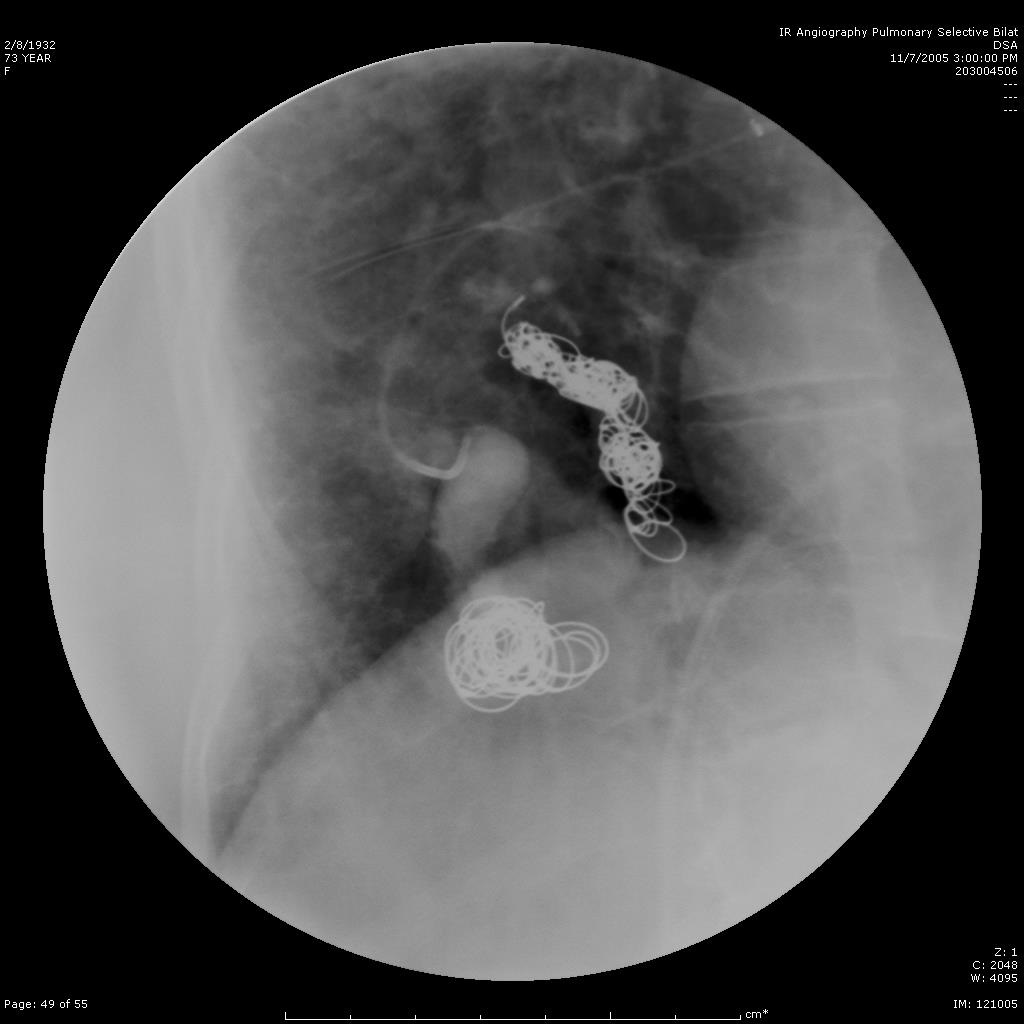

肺动静脉畸形

|

|

|

肺动静脉畸形分为单发、多发和弥漫性 |

这一例为多发性肺动静脉畸形 |

|

|

|

显示巨大静脉池显影 |

回流至肺静脉 |

肺动静脉畸形

|

|

|

|

选择其中一支畸形的滋养动脉 |

造影剂经静脉池回流至肺静脉 |

造影剂经静脉池回流至肺静脉 |

|

|

|

|

栓塞开始:先致密填塞静脉池,再致密栓塞滋养动脉 |

造影显示部分静脉池不显影,滋养动脉闭塞 |

选择性肺动脉造影显示另一支滋养动脉和静脉池。 |